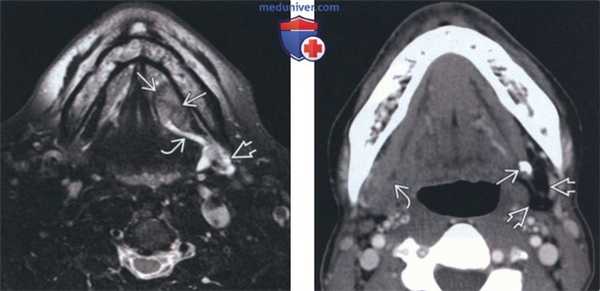

(Слева) На аксиальной МРТ (Т2 ВИ FS) у пациента с ПКР слизистой оболочки определяется образование дна полости рта слева с четко очерченными контурами. Образование приводит к обструкции протока левой поднижнечелюстной железы; определяется вторичное воспаление левой ПНЖ, имеющей высокую интенсивность сигнала.

(Справа) На аксиальной КТ с КУ на уровне дна полости рта у пациента с «образованием» поднижнечелюстной области справа визуализируется плотный конкремент в проксимальных отделах протока в области ворот левой ПНЖ. Обратите внимание на выраженную жировую атрофию и хронический сиаладенит слева. «Образование» справа - нормальная ПНЖ.